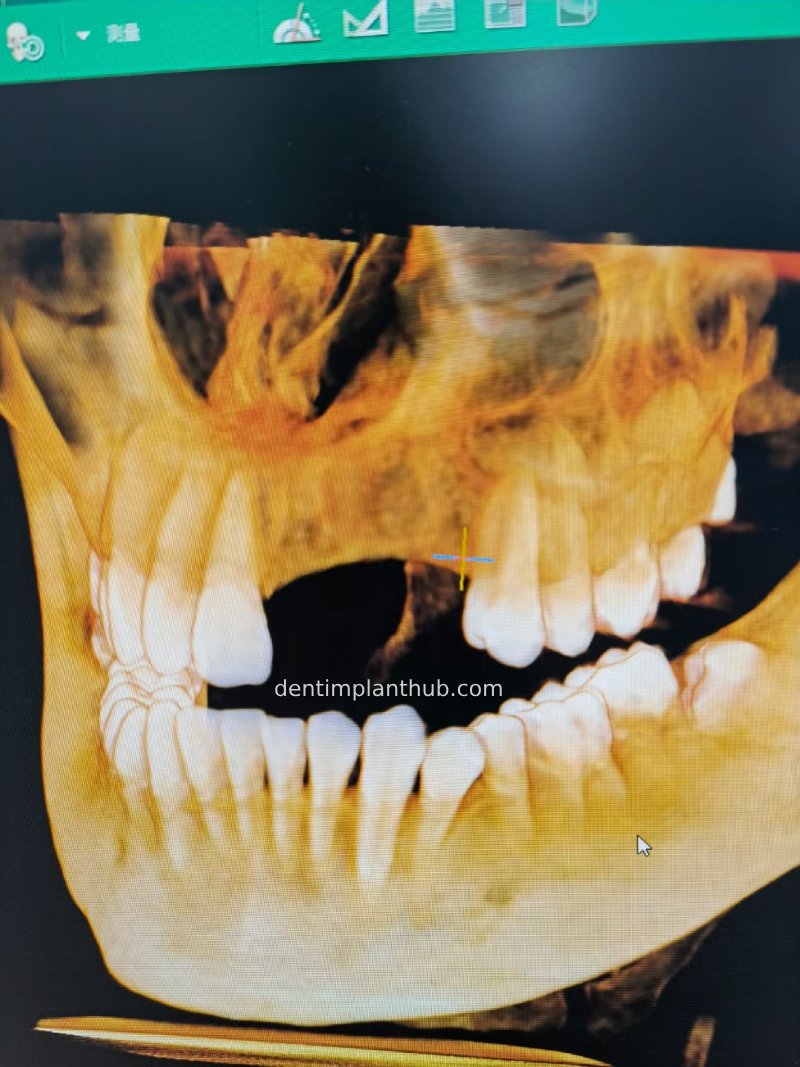

Case 2: 21~23 bone split implantation of two implants

The patient's left maxillary teeth 1, 2 and 3 were dislodged due to trauma 4 months prior to surgery, and at the same time, due to a fracture of the alveolar eminence, the bone width was only 3 mm, and bone splitting horizontal bone augmentation surgery was performed

Three-dimensional CT view before surgery